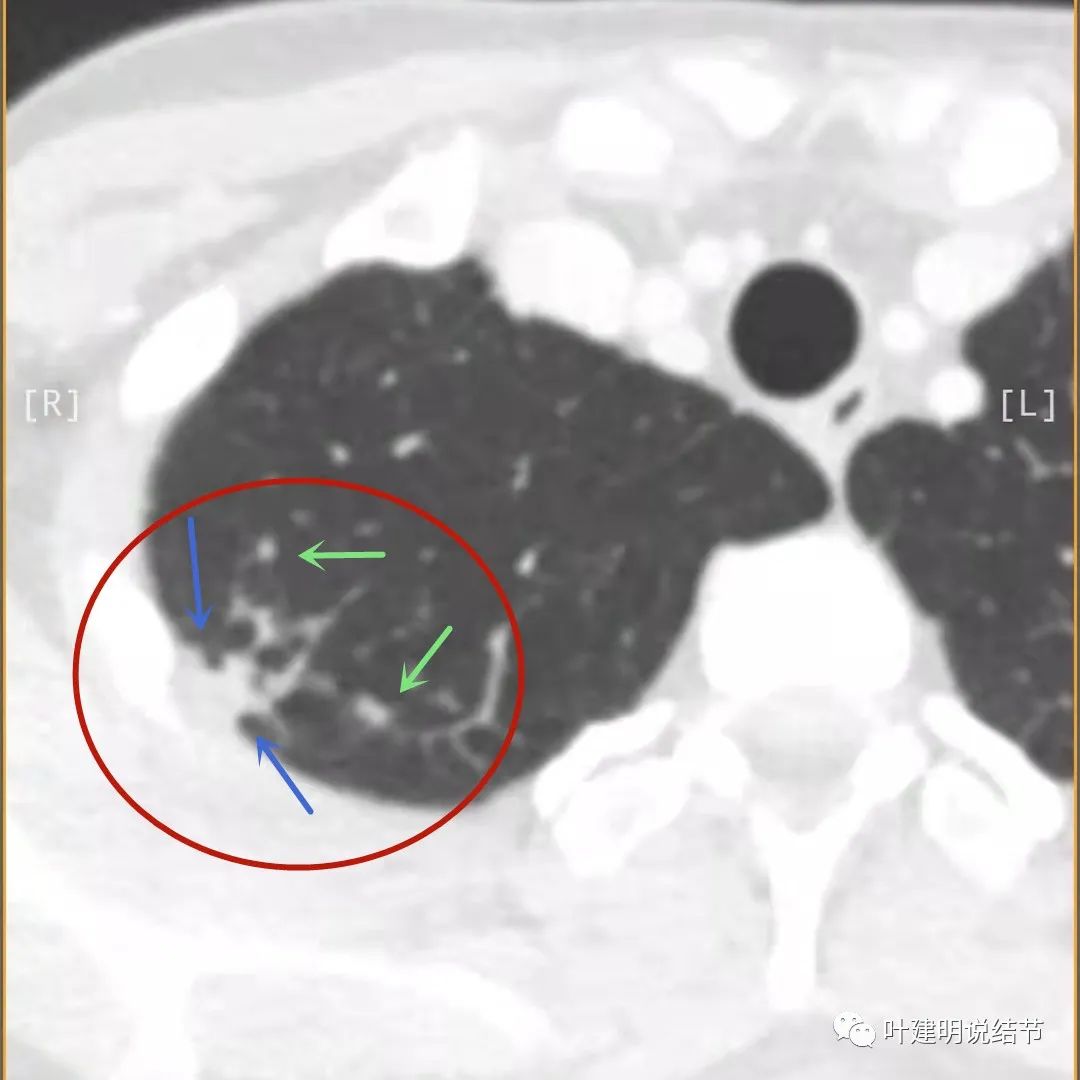

再看影像印象:病灶较1年前有所进展,部分层面像恶性,囊壁厚薄不均,内面有小突起。但邻近胸膜增厚,旁边的磨玻璃部分散且淡,边界不清,实性部分边相对较光,囊壁有点状过高密度。良性可能性大些,恶性不能除外。

我们再来看薄层的CT图像:

病灶出现,模糊的磨玻璃影

部分密度过高,且呈条状

邻近胸膜有增厚(蓝色箭头),主病灶边界较清(红色箭头),实性部分密度过高(粉色箭头),旁边有磨玻璃影,散且模糊(砖色箭头)